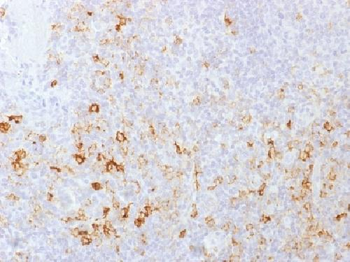

Formalin-fixed, paraffin-embedded human Tonsil stained withCD162 Monoclonal Antibody (PSGL1/1601).